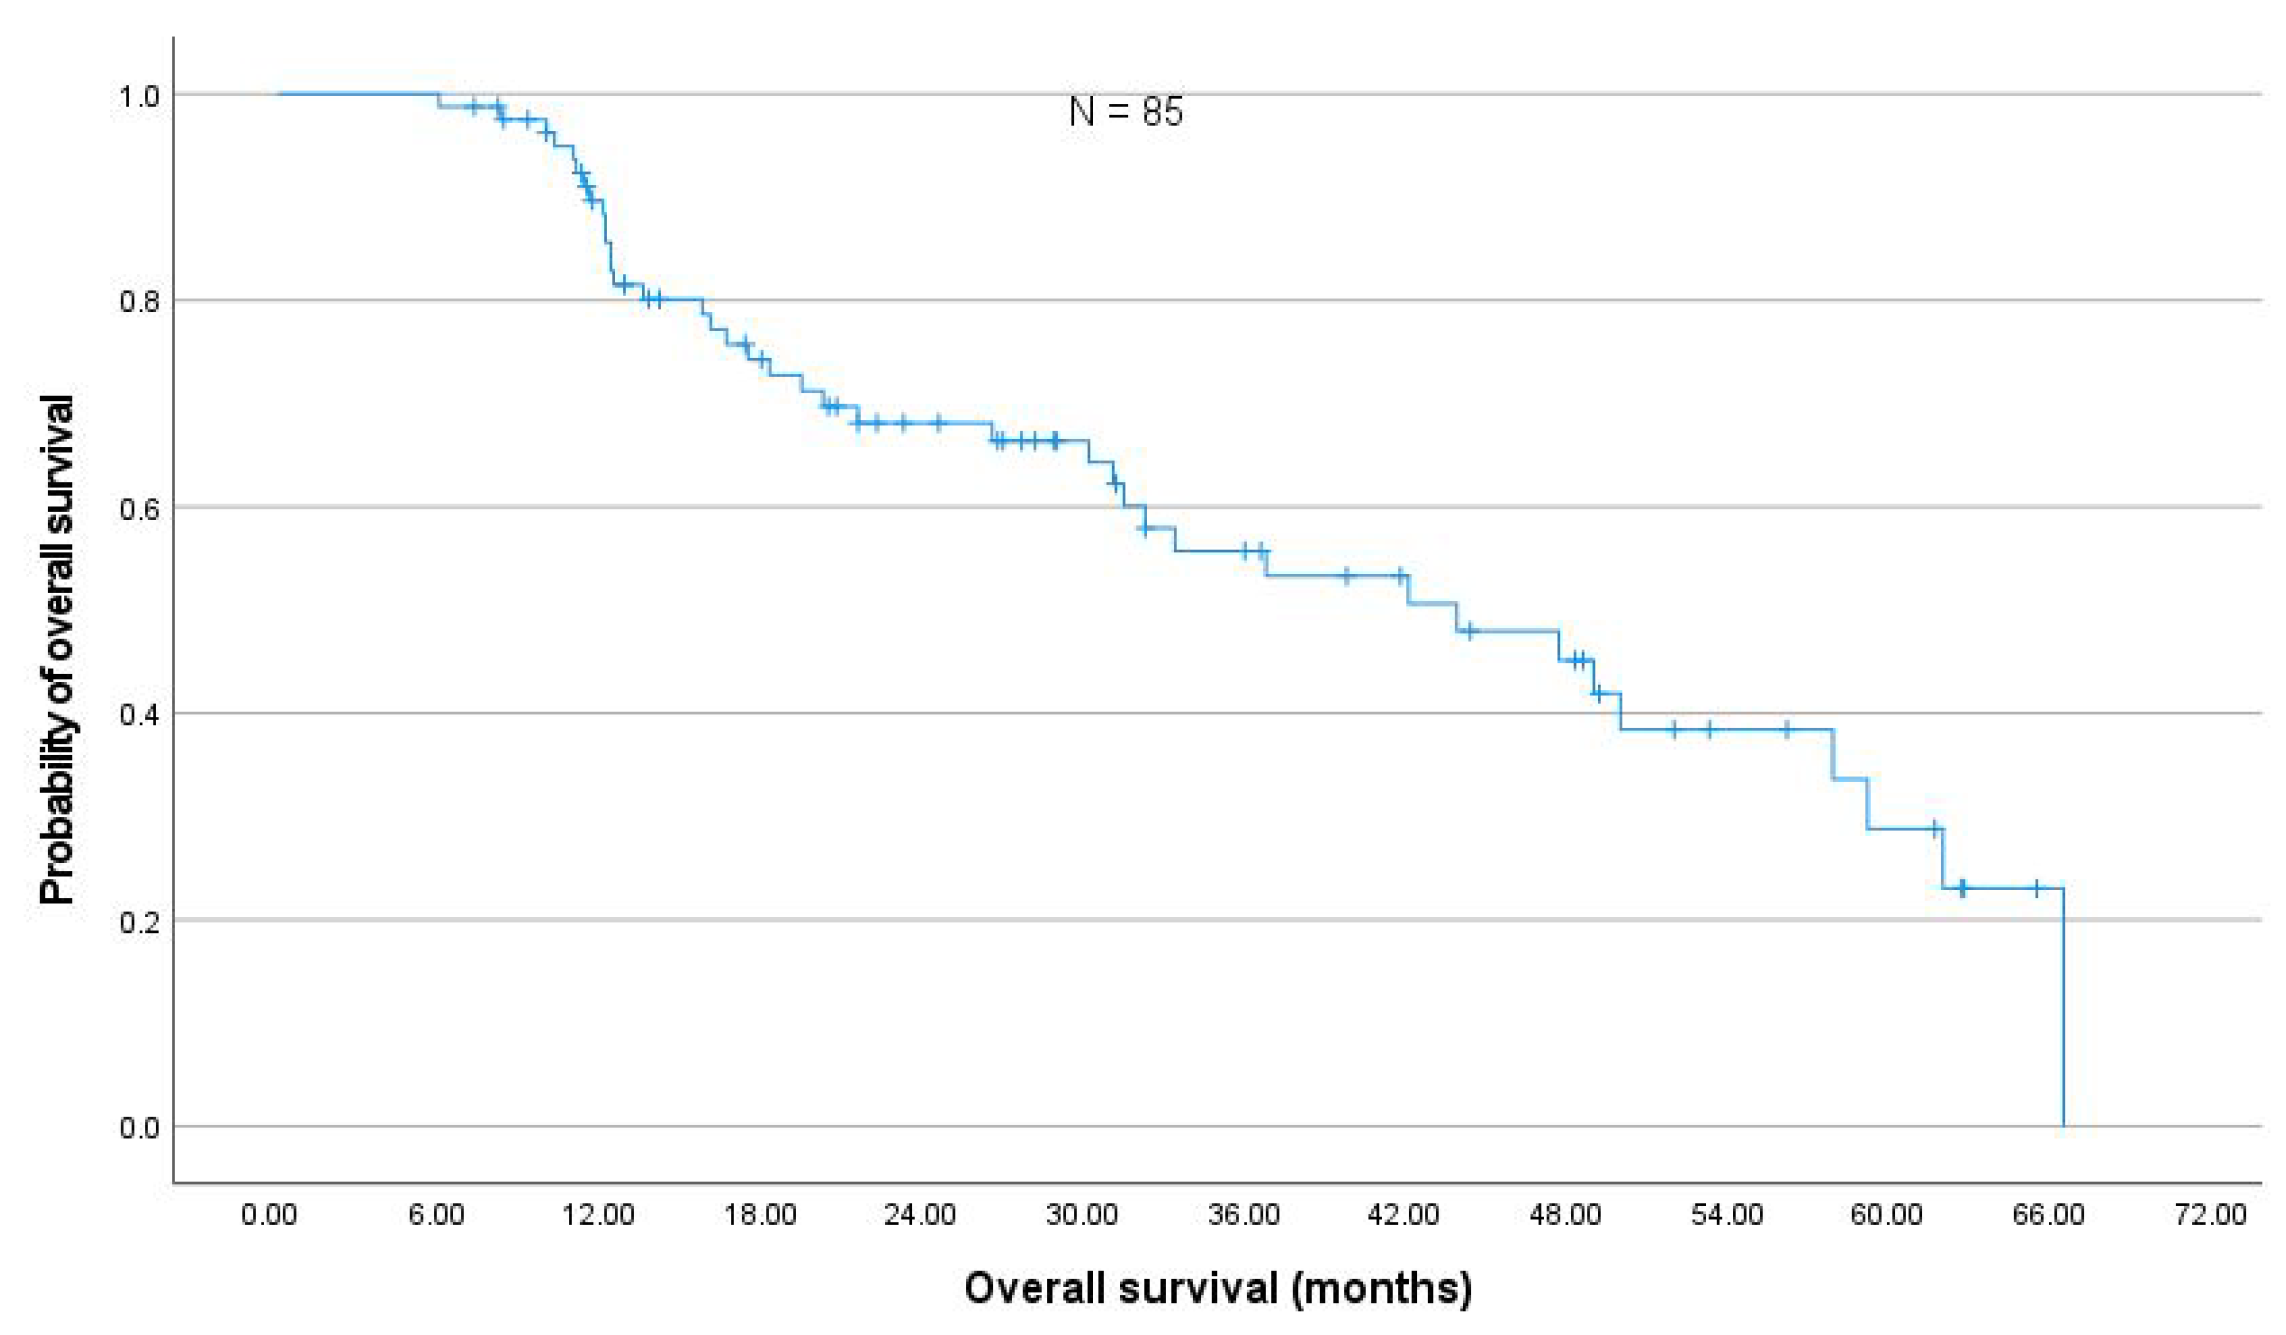

3.4. Toxicity